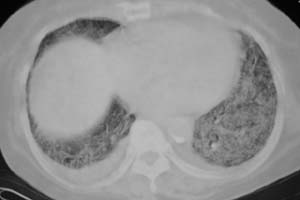

以下是引用liaizhi在2007-7-6 0:05:00的发言:[br]双肺纹理膜糊,沿纹理走行有班点状高密度影。考虑心衰并肺水肿。

以下是引用andymaomao在2007-7-5 22:23:00的发言:[br]双上肺明显,考虑心衰并肺水肿,双侧胸腔少量积液!另不除外肺泡蛋白沉着症及肺泡ca可能。[br]联想机制——心脏病(代偿期)--肺部淤血--后可能并感染致病情加重--抗炎治疗好转,但肺淤血严重,心功能失代偿--心衰而死亡!

以下是引用拾荒者在2007-7-6 13:06:00的发言:[br]支持:心衰,肺水肿及ards